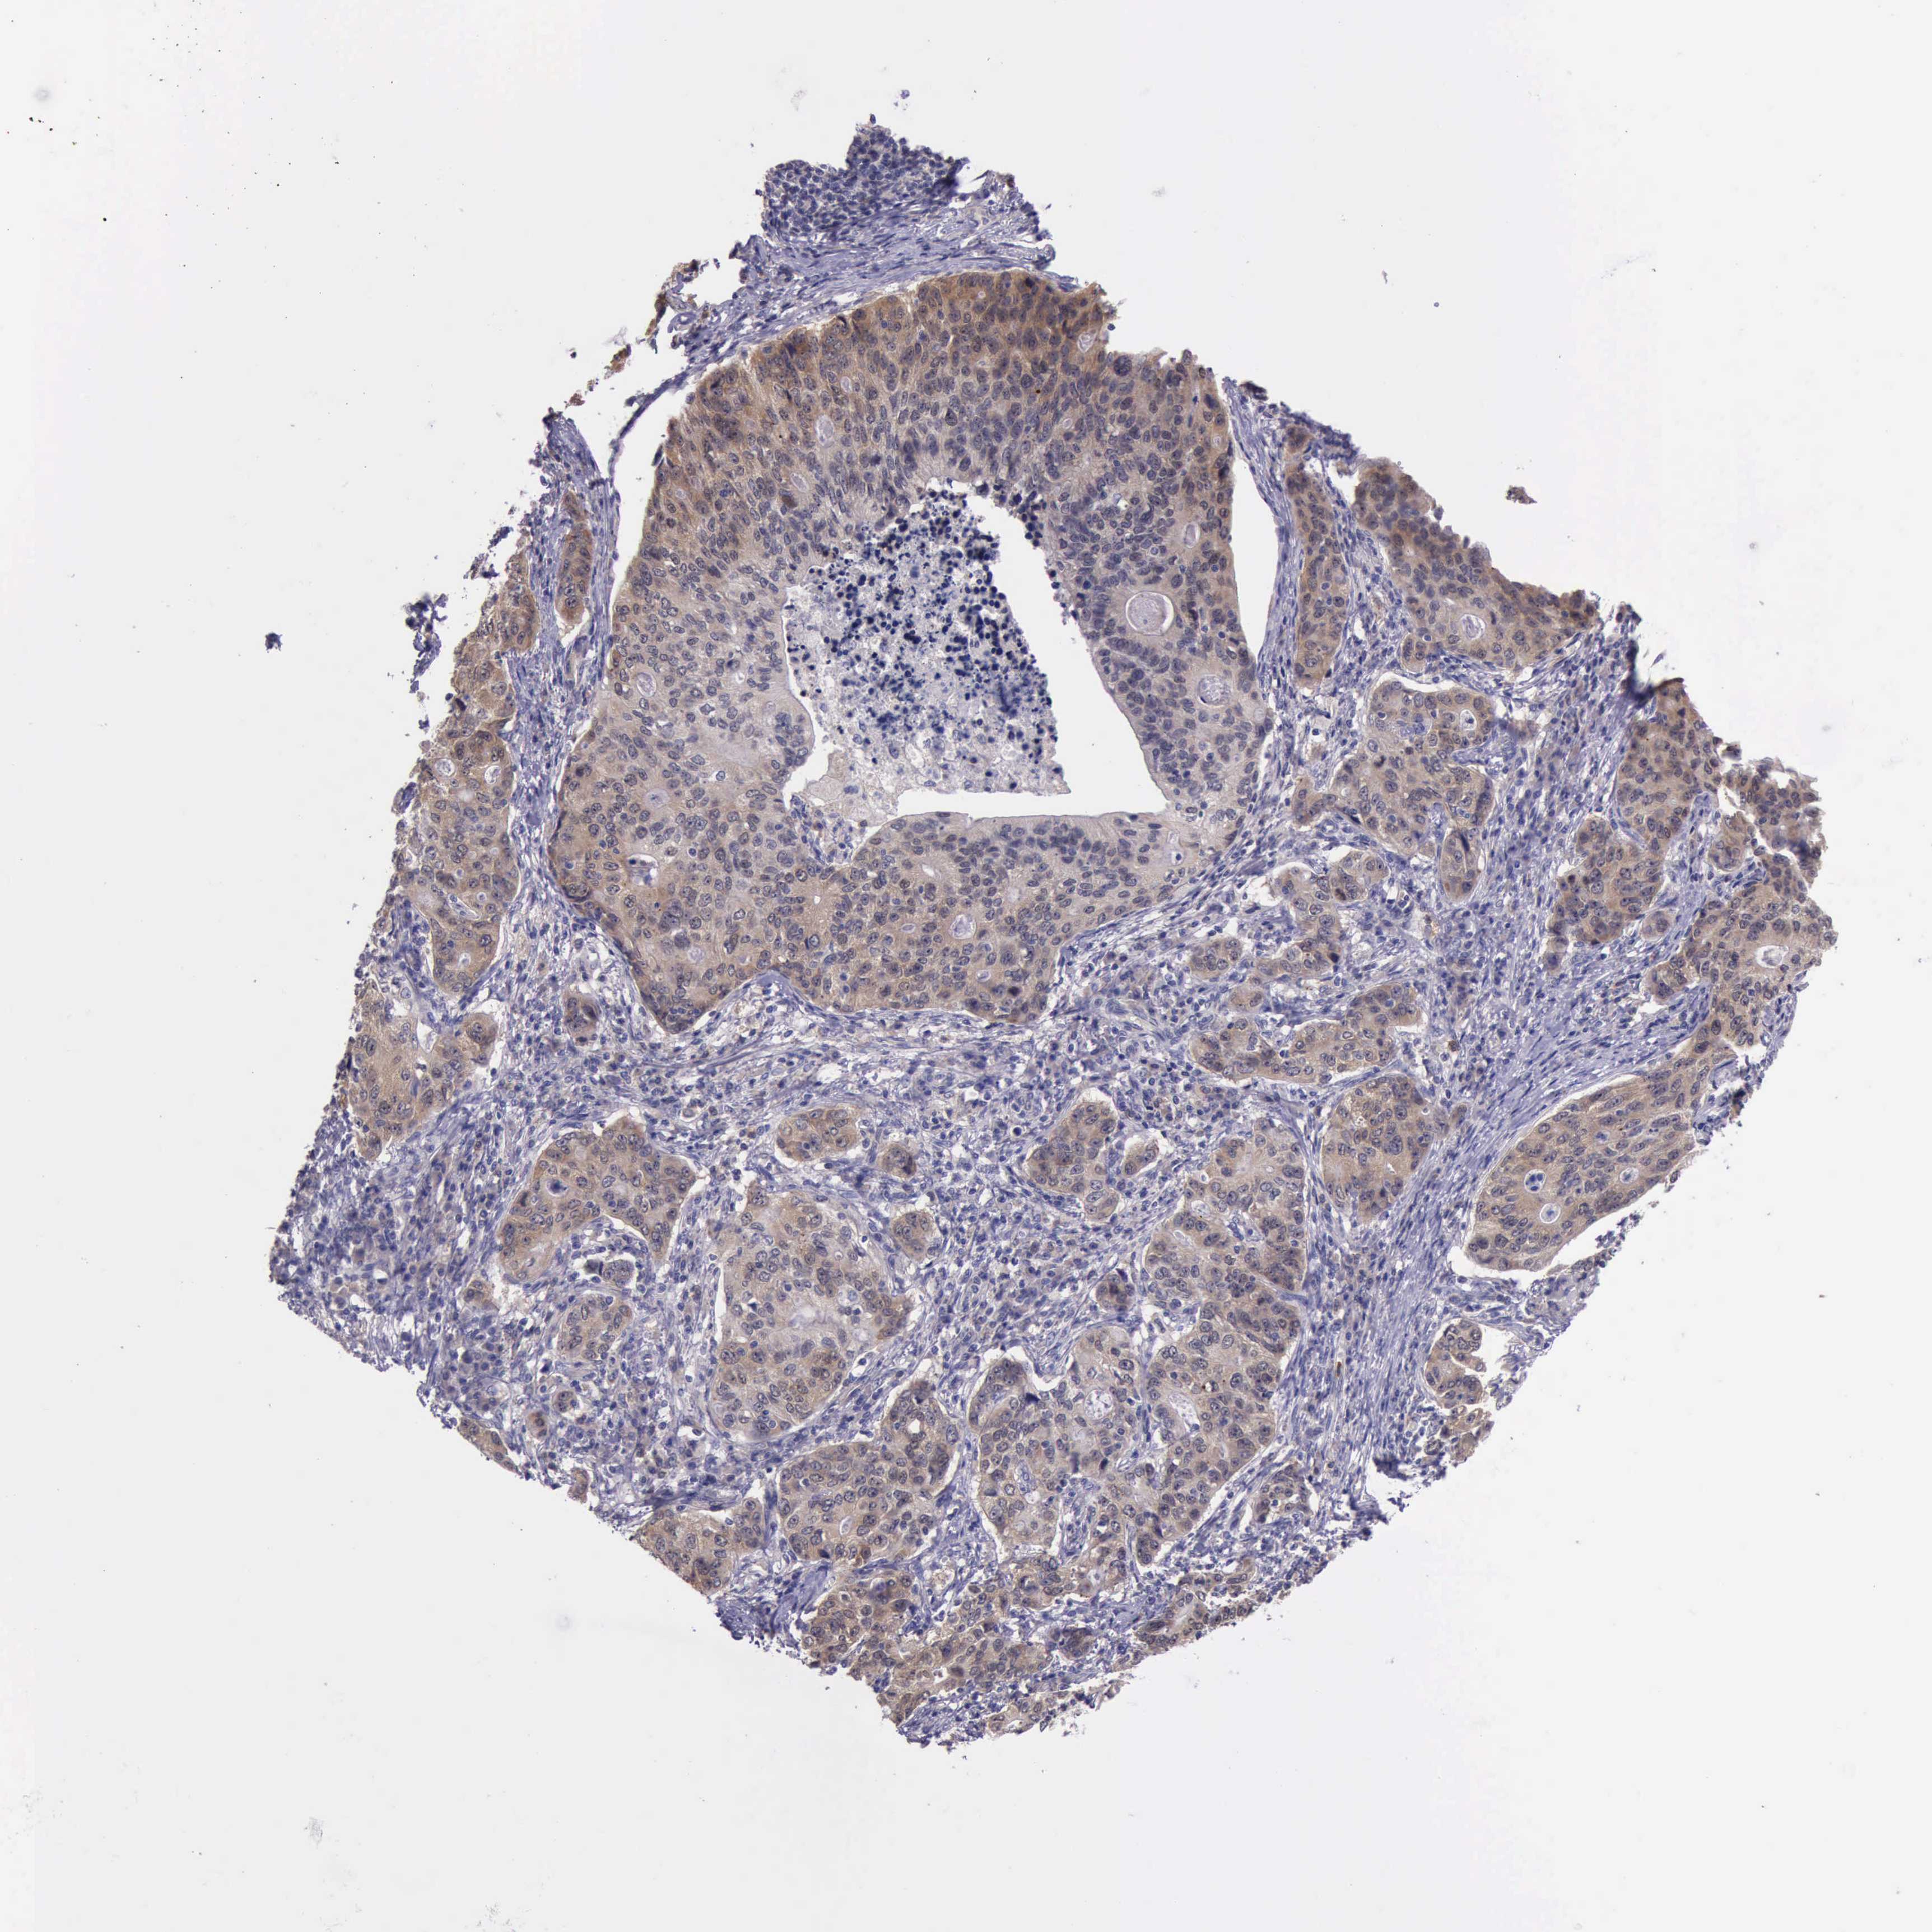

STOMACH CANCER - Protein expressioni

A mouse-over function shows sample information and annotation data. Click on an image to view it in a full screen mode. Samples can be filtered based on level of antibody staining by selecting one or several of the following categories: high, medium, low and not detected. The assay and annotation is described here.

Note that samples used for immunohistochemistry by the Human Protein Atlas do not correspond to samples in the TCGA dataset.

Antibody stainingi

Antibody staining in the annotated cell types in the current human tissue is reported as not detected, low, medium, or high, based on conventional immunohistochemistry profiling in selected tissues. This score is based on the combination of the staining intensity and fraction of stained cells.

Each image is clickable and will lead to virtual microscopy that enables deeper exploration of all samples and also displays staining intensity scores, fraction scores and subcellular localization as well as patient and tissue information for each sample.

Antibody HPA001208

Staining

High

Medium

Low

Not detected

Intensity

Strong

Moderate

Weak

Negative

Quantity

>75%

75%-25%

<25%

None

Location

Nuclear

Cytoplasmic/membranous

Cytoplasmic/membranous,nuclear

Adenocarcinoma, NOS